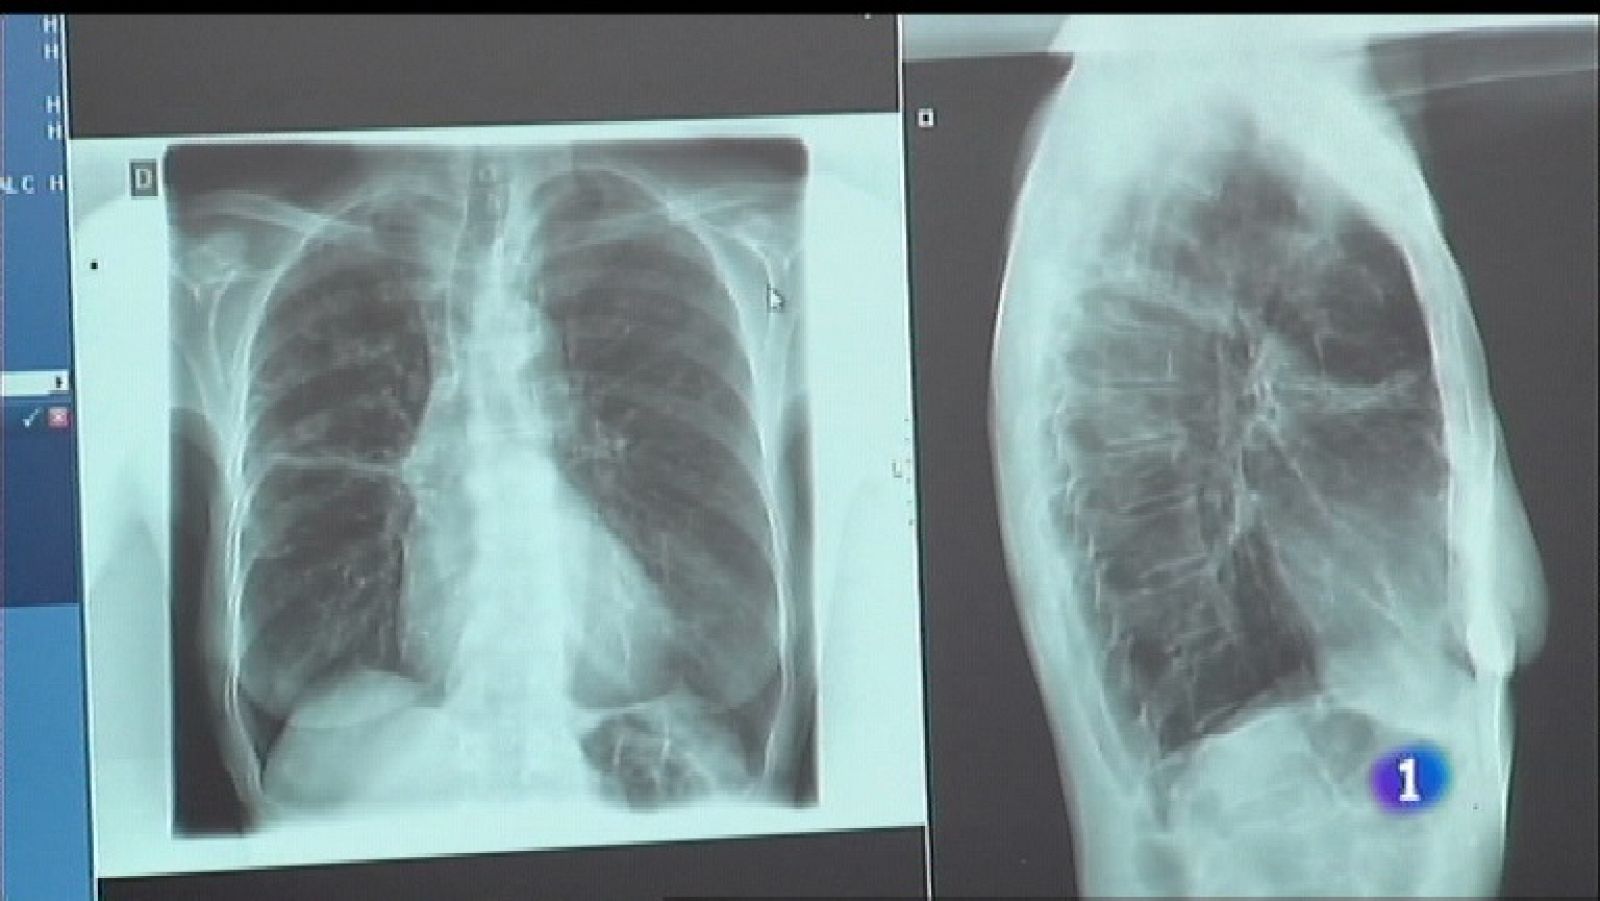

Se reduce la incidencia de la tuberculosis en Asturias.Tensión a las puertas del Congreso, donde esta mañana se concentraban trabajadores de Alcoa,...

Se reduce la incidencia de la tuberculosis en Asturias.Tensión a las puertas del Congreso, donde esta mañana se concentraban trabajadores de Alcoa, con carga policial y una persona detenida. El parlamento asturiano celebra el último pleno de la legislatura, con despedida de los 6 portavoces parlamentarios, que no repiten en las listas electorales.